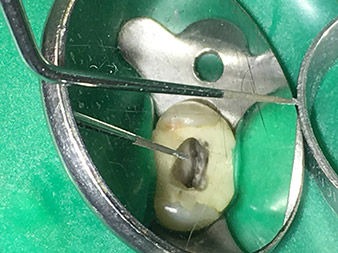

Neben effizienten Diagnose- und Behandlungsmethoden zählt der Einsatz neuester technischer Hilfsmittel und Instrumente zu den wichtigen Bausteinen einer erfolgreichen Patienten-Betreuung. Pro Woche kümmert sich Dr. Shahrad Nouraie Ashtiani zusammen mit seinem Team in der Praxis in Bremen (Deutschland) um bis zu zehn Endofälle. Die Forderung der Patienten nach einer möglichst schonenden Behandlung sowie guten Erfolgsprognosen bedeutet für den Zahnarzt und Weiterbildungsassistenten der Oralchirurgie mit Tätigkeitsschwerpunkt Endodontie eine tägliche Herausforderung.

Als Anwender des erweiterten W&H Instrumenten-Sortiments für die Ultraschall-Endodontie gelingt es Dr. Nouraie Ashtiani Wurzelkanalbehandlungen nicht nur effizienter, sondern vor allem mit weniger Belastung für den Patienten durchzuführen. Selbst schwierige Situationen werden vom Experten mühelos gemeistert. In einem Interview spricht der Endodontie-Spezialist über die besonderen Eigenschaften der W&H Instrumente und verweist auf mögliche Risiken in der Wurzelkanalbehandlung.

Dr. Nouraie: Besonders gerne arbeite ich mit der Spitze 1E. Diese eignet sich hervorragend zur Aktivierung der Spülflüssigkeit im Wurzelkanal. Durch die feine Gestaltung dieser Spitze kann man damit auch tiefe Kanalabschnitte erreichen und hier eine optimale Aktivierung gewährleisten.

Dr. Nouraie: Ich habe mehrere Lieblingsspitzen. Meine absolute Lieblings- und Muss-Spitze ist die Spitze 1E. Diese findet ihre Indikation wirklich bei jeder Wurzelkanal-Behandlung, da mit dieser die Spülflüssigkeit aktiviert wird. Es ist bekannt, dass die Wurzelkanalspülung neben der Aufbereitung die wichtigste Komponente der Behandlung darstellt. Eine aktivierte Spülflüssigkeit dringt tiefer in die Dentin-Kanälchen ein und kann somit eine bessere Wirkung erzielen. Somit spielt die Aktivierung der Spülflüssigkeit für die Verbesserung der Qualität einer solchen Behandlung eine wichtige Rolle.